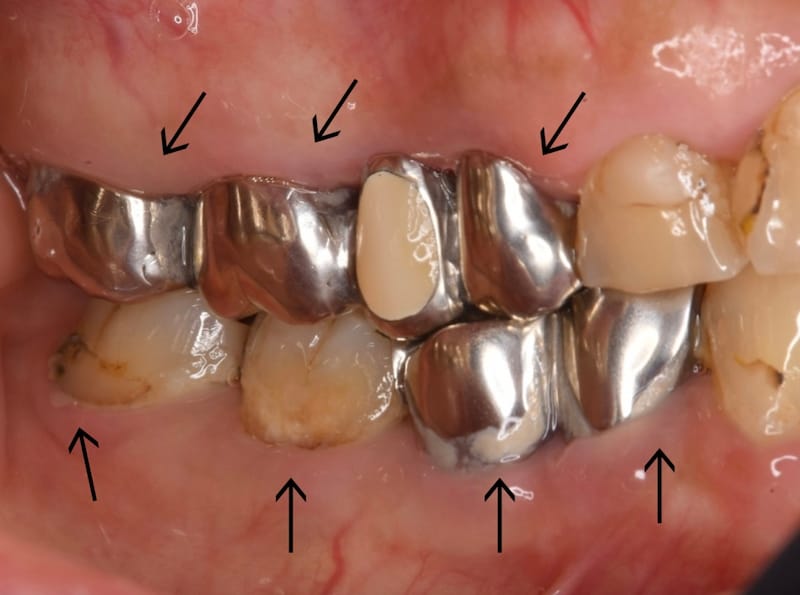

「歯医者に通っても通っても、すぐむし歯ができる」「治療を行った歯が、またむし歯になった」という経験がある方には、「むし歯になる原因」が必ずあるのです。今回は実際の患者さんのケースを基に、なぜむし歯ができるのかを皆さんと考えたいと思います。

一度むし歯になって治療で削った歯は、一度も治療していない歯と比べても、再びむし歯になるリスクが高いです。また、歯は治療を重ねるごとに、その歯を失うリスクとがどんどん大きくなります。むし歯になってから治療、再治療を重ねるのではなく、むし歯にならないために生活習慣を整え、予防のために歯科医院を活用することが重要です。皆さんもぜひ、すぐに始められることから、効果的なむし歯予防法を取り入れてみてください。